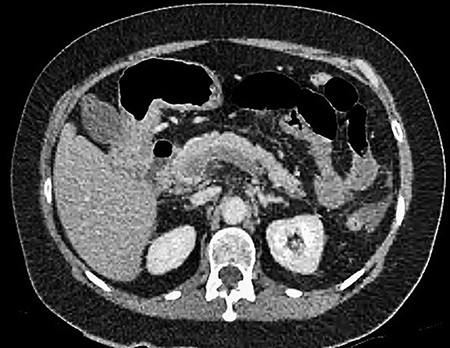

A 61-year-old female presented to a regional hospital with a 3-week history of intermittent diarrhoea, vomiting and generalized abdominal pain. She had a diffusely tender abdomen but was not peritonitic, and was shocked with a heart rate of 110 beats per minute, blood pressure of 89/45 mmHg and was peripherally cool. Her blood tests revealed a lactate of 7.2 mmol/L, which worsened to 7.8 mmol/L during resuscitation with intravenous fluids, and white cell count was 30.9 × 109/L, with an international normalized ratio (INR) of 1.4. She had an acute kidney injury with a creatinine of 119μmol/L and estimated glomerular filtration rate (eGFR) of 43 mL/min/1.73m2. Computed tomography (CT) revealed extensive thickened loops of non-enhancing small bowel with pneumatosis, moderate free fluid and a large splenic infarction. There was extensive thrombosis of the splenic vein and superior mesenteric vein extending into the portal vein to the level of the porta hepatis. Her background history included factor V Leiden and protein S deficiency, for which she had been non-compliant with warfarin during this illness. She had no surgical history (Figs. 1–5).

CT showing multiple thick-walled, non-enhancing loops of small bowel.